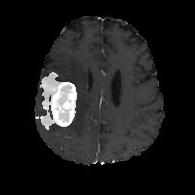

We argue that the sub-optimal paradigm of processing different abstractions within a single CNN pipeline can be remedied through the effective processing of information in a structured manner. Consequently, we devise strategies for disentangling the edge and texture information within a single training pipeline. Figure 2 illustrates how our proposed module, dubbed EG-CNN, can be paired with any existing CNN encoder-decoder to improve segmentation quality near intensity edges. We have applied our EG-CNN to the tasks of brain and liver tumor segmentation in medical images (Figure 3).

(1) Brain MR (2) Liver MR (3) Liver CT (4) Lung CT